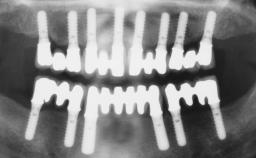

Immediate Loading of Six Implants in the Mandible and Six Implants in the Maxilla and Final Restoration with Full-Arch CAD/CAM Metal Framework FDPs Involving Digital Planning and Guided Surgery

# of Implants 12

Type of Implants One-Piece

Guided Surgery Yes

Bone Volume Horizontally and vertically sufficient